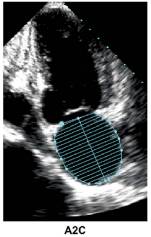

3、HFpEF—左室收缩功能评估

注:LVEDVI (LV end-diastolic volume index) ,左心室舒张末容积指数;

LVESVI ( LV end-systolic volume index),左心室收缩末容积指数.

4、左室收缩功能指标的正常值范围